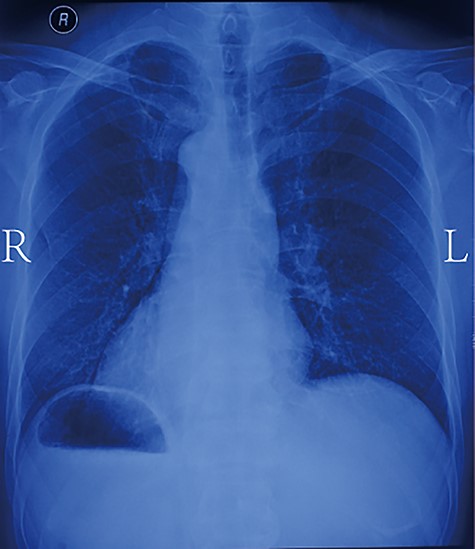

A 55-year-old man was admitted to hospital with progressive dysphagia. The patient was found to have mirror-image dextrocardia (Fig. 1) with an abnormally thickened esophageal wall (thoracic middle-lower segment) observed by way of contrast-enhanced computed tomography (CT) of the chest (Fig. 2a). SIT was observed in the patient, with a right-sided position of the heart and aortic arch (Fig. 2b). Additionally, the spleen and stomach were observed on the right side and the liver on the left by means of CT of the upper abdomen (Fig. 2c). Based on the preoperative examination, the patient was diagnosed with esophageal carcinoma, which was clinically staged as T3N0M0, stage IIA (Union for International Cancer Control esophageal carcinoma pathological stage, 2017). Laparoscopic and thoracoscopic esophagectomy with intrathoracic anastomosis was determined to be the best treatment for the patient’s middle-lower esophageal carcinoma. Throughout the laparoscopy-assisted abdominal surgery, the patient was placed in a supine position. The surgeon stood on the left side of the patient, which is the opposite of the standard position. Under the laparoscope, in accordance with preoperative imaging, the stomach was observed in the right hypochondriac region, the spleen to the right and rear of the stomach, and the liver on